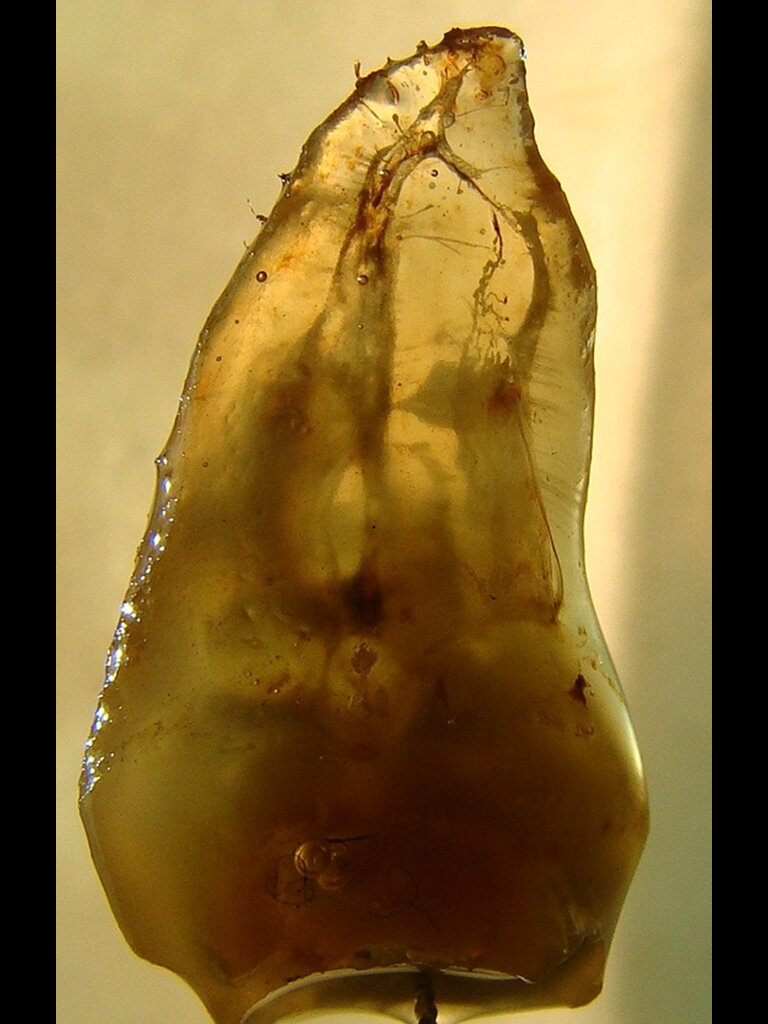

Fig. 4: Cleared tooth showing the true complexity of the anatomy within this molar tooth. (Courtesy of Dr. Sergio Rosler)

Managing complex anatomy is much simpler if the clinician has a pre-operative road map. The CBCT provides the roadmap and the surgical microscope the lens (literally) through which to visualize the result. Aside from a relaxed patient who is profoundly numb, being able to visualize anatomy by taking a pre-operative (and possibly intra-operative) CBCT and using a surgical microscope during treatment have no substitutes. They are the current “Gold Standard” in that 3-D imaging shows the clinician the true reality of a clinical situation as opposed to the suggestion gained from a 2-D radiograph. Proper interpretation of imaging prior to and/or during endodontic treatment goes a long way in taking the “guesswork” out of identifying canal location and other anatomical complexities as the procedure unfolds. In a 2014 study by El Fayad and Johnson, it was determined that when having a pre-operative CBCT as compared to 2-D radiographs alone, the treatment plan was modified 62 percent of the time. This is a huge game changer to think that the information learned from 3-D imaging changed the plan of treatment over six times out of 10 (Fig. 4).[2]